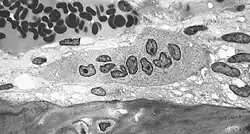

Osteoklasten sind große Zellen mit einem Durchmesser von 50 bis 100 µm, die bis zu 10 Zellkerne enthalten können. Sie finden sich an der Knochenoberfläche in den Resorptionslakunen (Howship-Lakunen). Genauso wie die eng mit ihnen verwandten Makrophagen sind sie in der Lage, sich amöboid fortzubewegen.

Der apikale Pol eines Osteoklasten ist dem Knochen zugewandt. Hier lassen sich verschiedene Bereiche unterscheiden:

- Zentral findet sich eine helle, streifige und vesikelreiche Zone, in der die Zellmembran in Form eines Bürstensaums stark gefaltet ist. Sie wird als ruffled border bezeichnet und ist der eigentliche Ort der Knochenresorption. Lichtmikroskopisch stellt sie sich hell-gestreift dar.

- In der Peripherie zeigt sich lichtmikroskopisch eine intensive Anfärbung. Dort haftet der Osteoklast mit seinem Adhäsionsapparat (Integrine) an der Knochensubstanz. Der Adhäsionsapparat besteht zumeist aus so genannten Podosomen. Es besteht ein sehr enger Kontakt zwischen Osteoklast und Knochen, mit einem Abstand von nur 0,3–0,5 nm. Man nennt diesen Bereich deshalb auch sealing zone.

- Das Zytoplasma, das die sealing zone umgibt, wird als clear zone bezeichnet, da es fast keine Zellorganellen aufweist. Dafür findet sich hier eine große Menge kontraktiler Proteine.